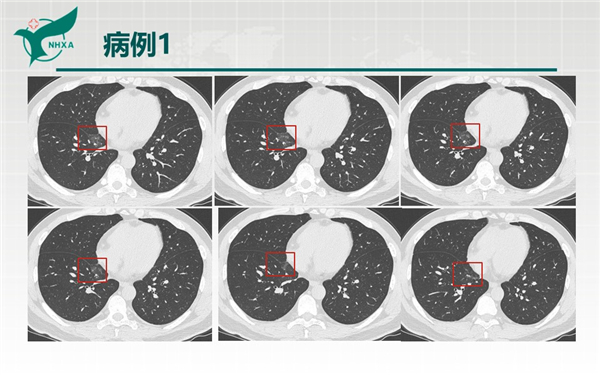

【病例分享】新型冠狀病毒肺炎3例(西安市第九醫(yī)院)

幻燈片2.jpg